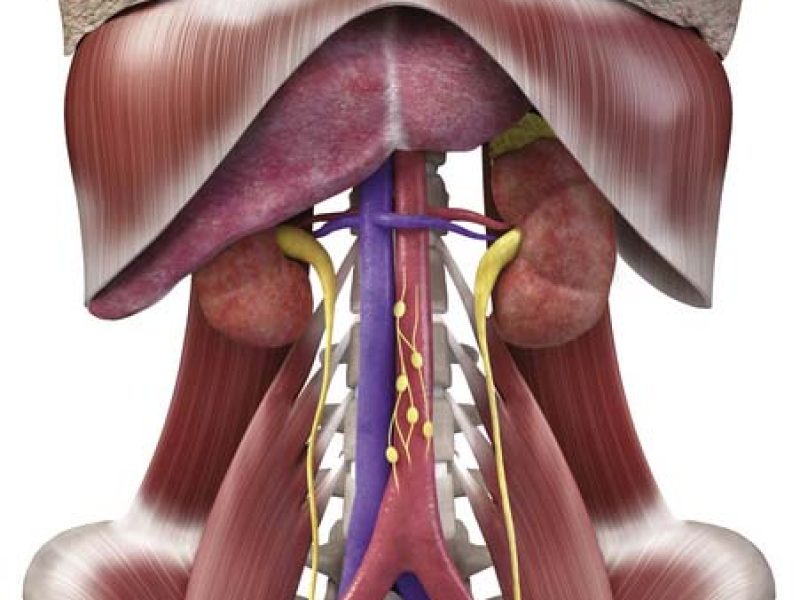

Innovative Oncology Services

Our Services

Oncology Services